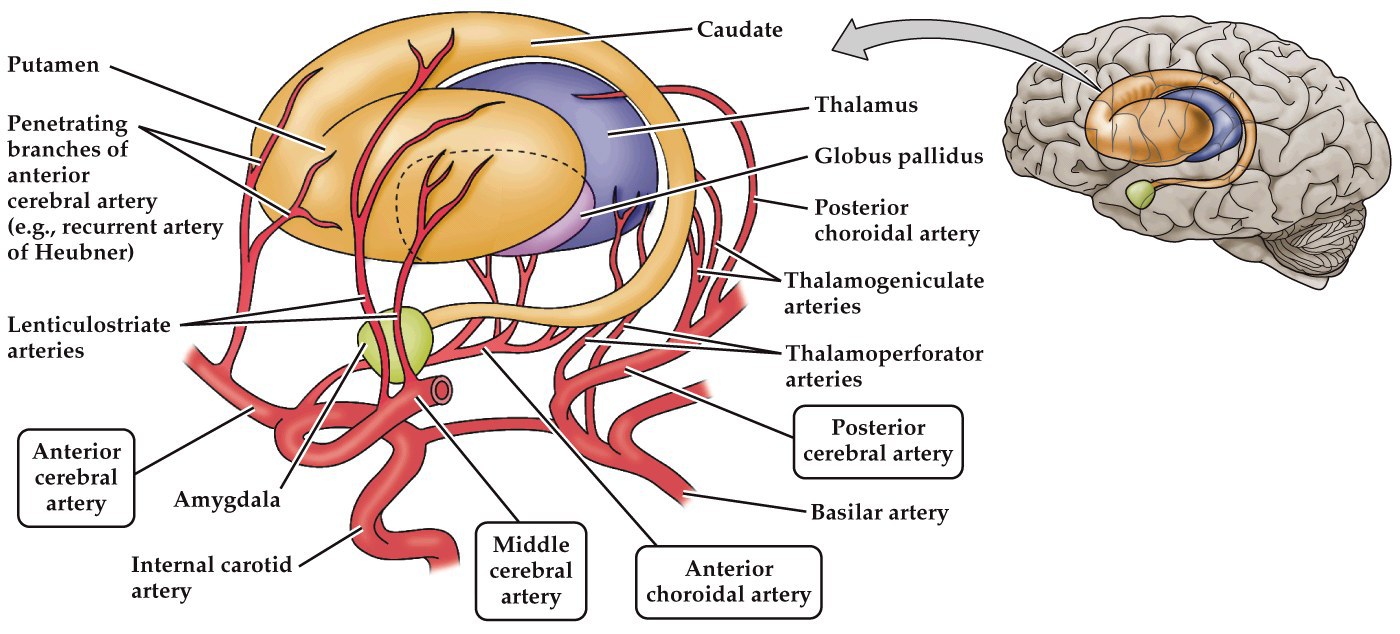

Cerebral circulation